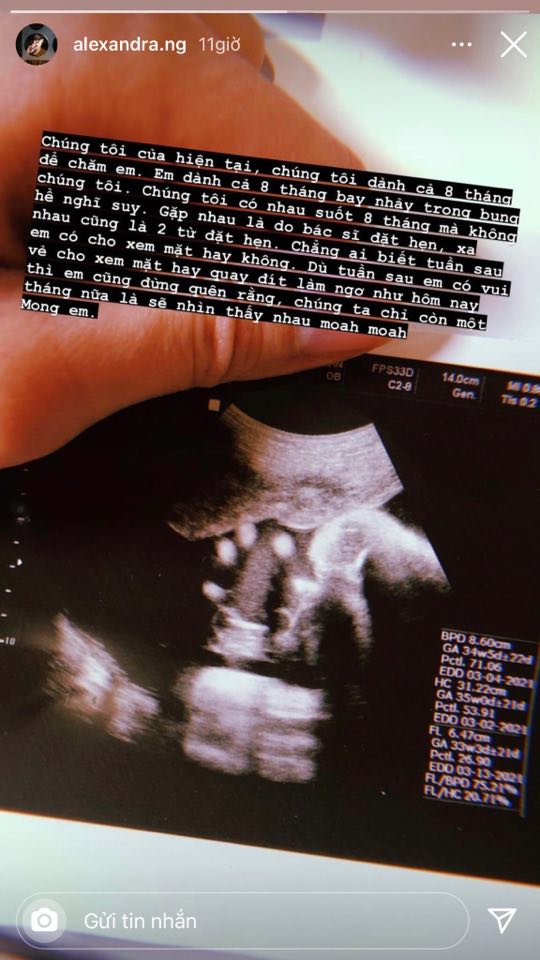

Trên trang cá nhân, Alex Nguyễn - người yêu đồng giới của An Nguy mới đây đã chia sẻ hình ảnh chụp siêu âm thai nhi.

Đi kèm với bức hình, Alex Nguyễn không quên để lại dòng trạng thái dài tiết lộ chuyện chỉ còn 1 tháng nữa em bé sẽ chào đời: "Chúng tôi của hiện tại, chúng tôi dành cả 8 tháng để chăm em. Em dành cả 8 tháng bay nhảy trong bụng chúng tôi. Chúng tôi có nhau suốt 8 tháng mà không hề nghĩ suy", Alex Nguyễn nhắn nhủ.

Người yêu đồng giới của An Nguy chia sẻ thêm: "Gặp nhau là do bác sĩ đặt hẹn, xa nhau cũng là 2 từ đặt hẹn. Chẳng ai biết tuần sau em có cho xem mặt hay không. Dù tuần sau em có vui vẻ cho xem mặt hay quay đít làm ngơ như hôm nay thì em cũng đừng quên rằng, chúng ta chỉ còn một tháng nữa là sẽ nhìn thấy nhau. Mong em".